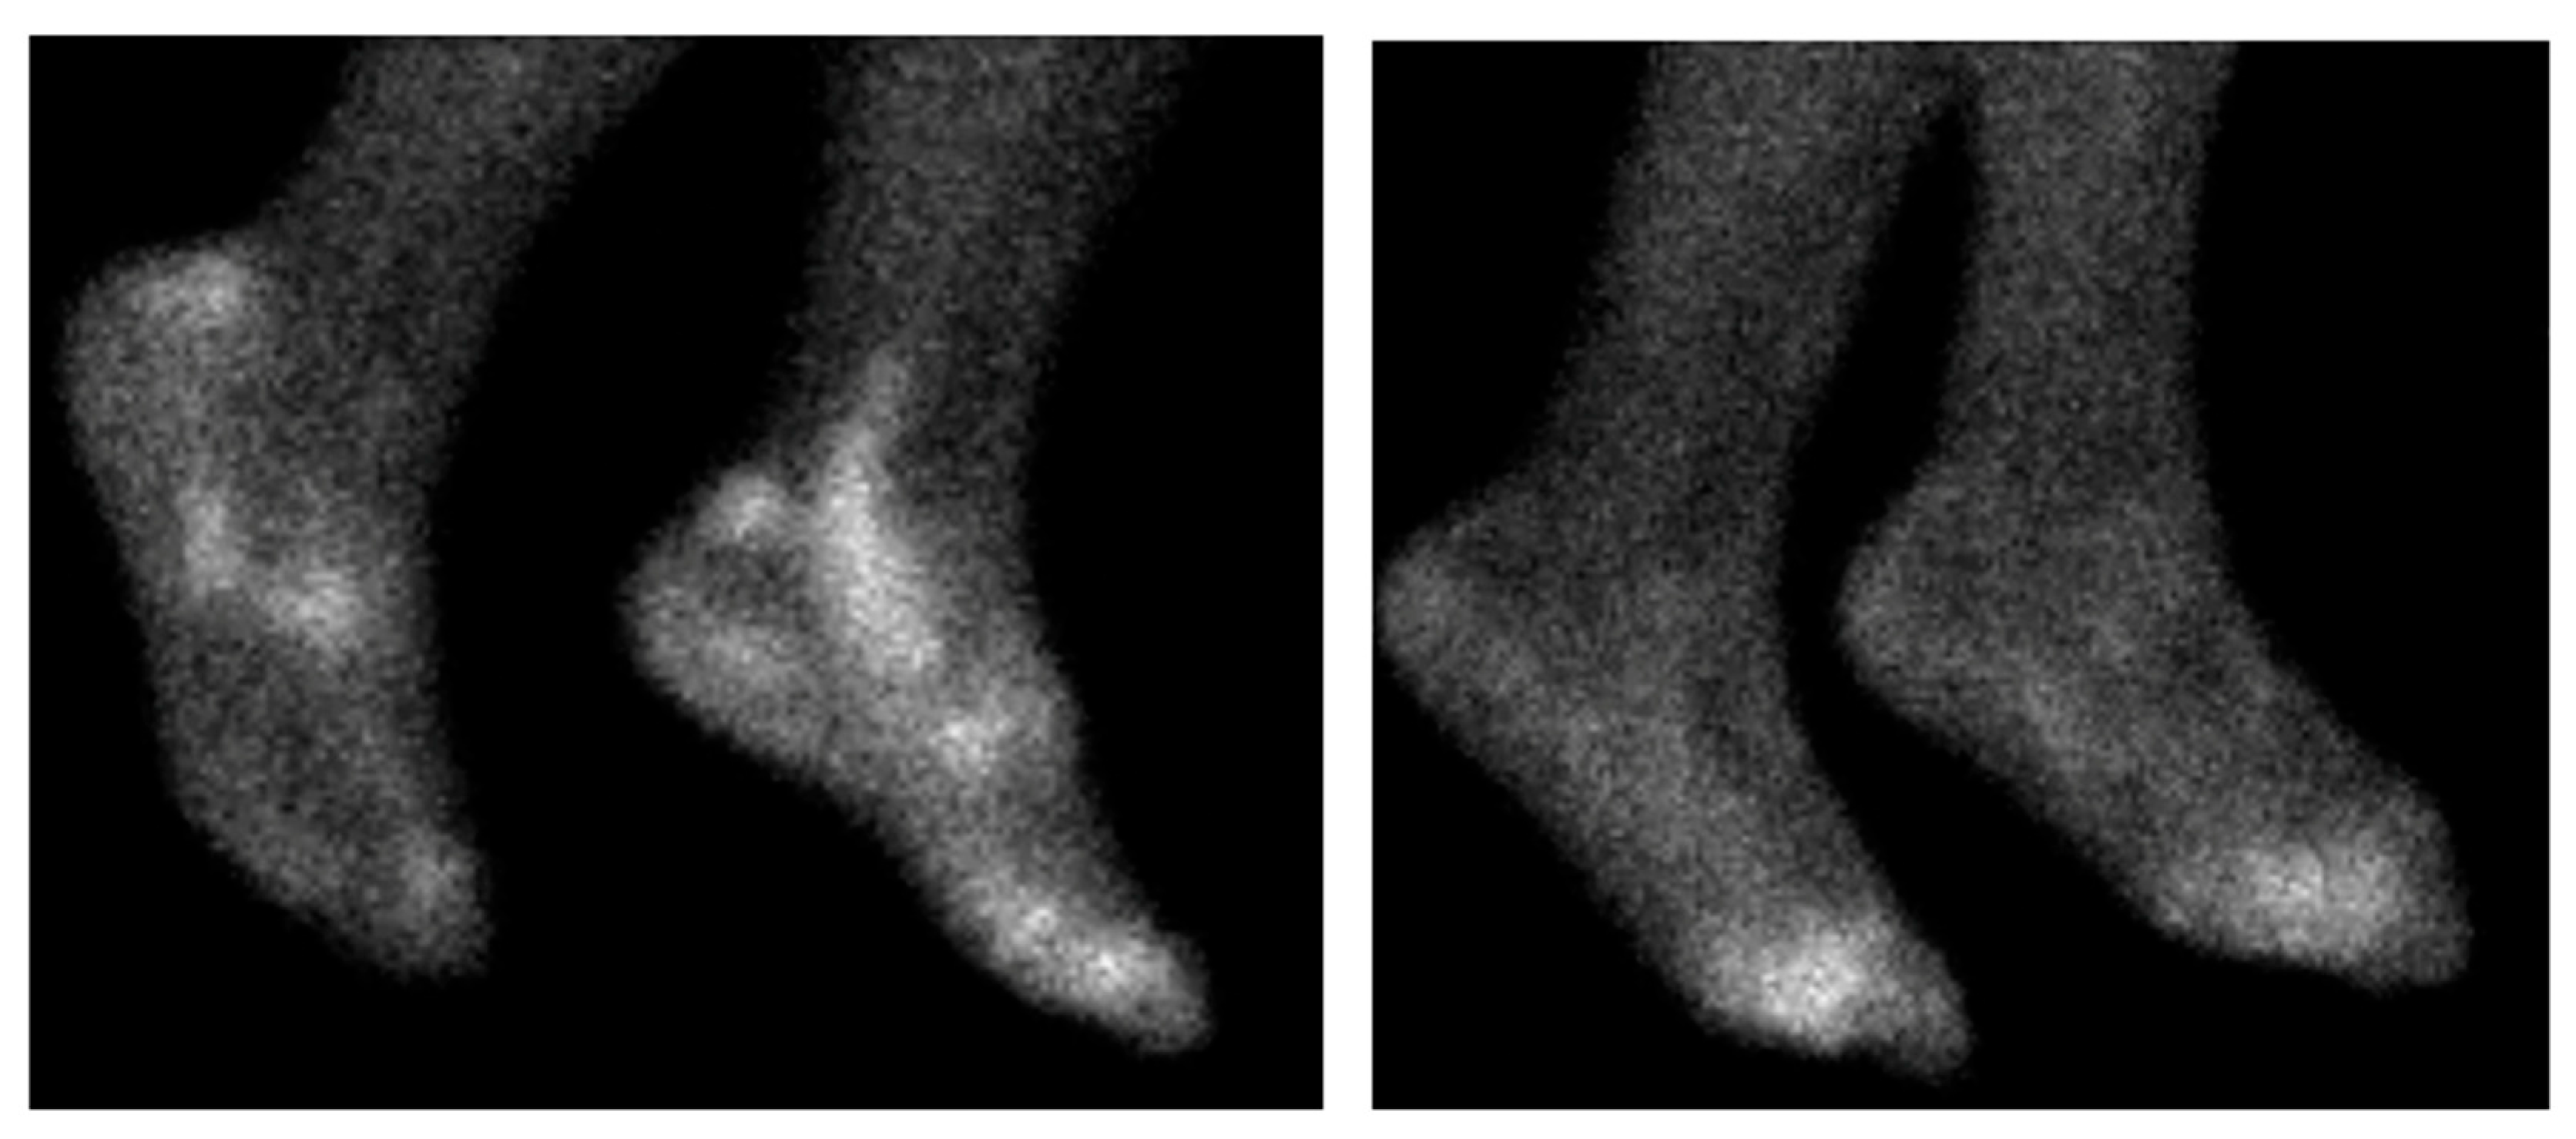

- Vogel, W.V.; van Riel, P.L.C.M.; Oyen, W.J.G. FDG-PET/CT can visualise the extent of inflammation in rheumatoid arthritis of the tarsus. Eur. J. Nucl. Med. Mol. Imaging 2007, 34, 439. [Google Scholar] [CrossRef]

- Watanabe, T.; Takase-Minegishi, K.; Ihata, A.; Kunishita, Y.; Kishimoto, D.; Kamiyama, R.; Hama, M.; Yoshimi, R.; Kirino, Y.; Asami, Y.; et al. (18)F-FDG and (18)F-NaF PET/CT demonstrate coupling of inflammation and accelerated bone turnover in rheumatoid arthritis. Mod. Rheumatol. 2016, 26, 180–187. [Google Scholar] [CrossRef] [PubMed]